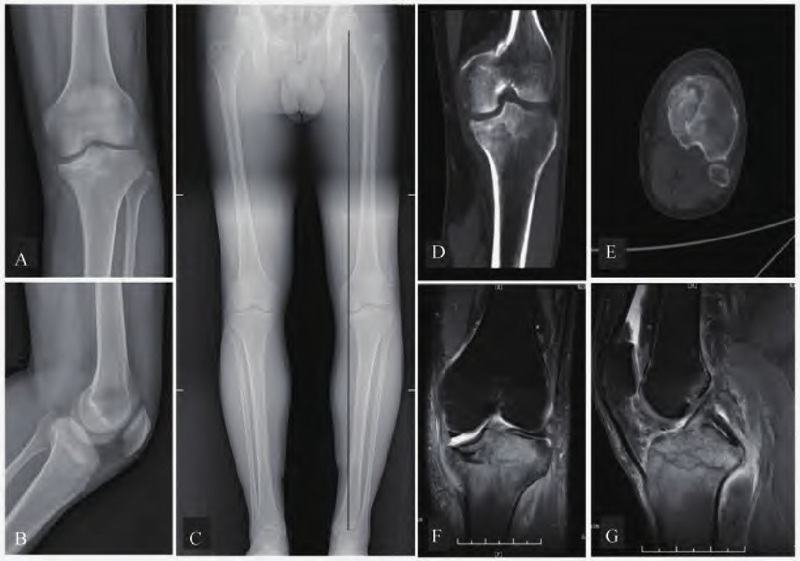

术前行X线、CT及MRI检查。膝关节正侧位及负重位下肢全长片提示胫骨内侧平台骨折,内翻畸形(图1 A-C)。CT检查进一步明确骨折累及范围和移位情况(图1 D-E)。MRI检查显示内侧平台塌陷,无交叉韧带损伤、半月板及侧副韧带损伤(图1 F-G)。

图1 术前影像学检查